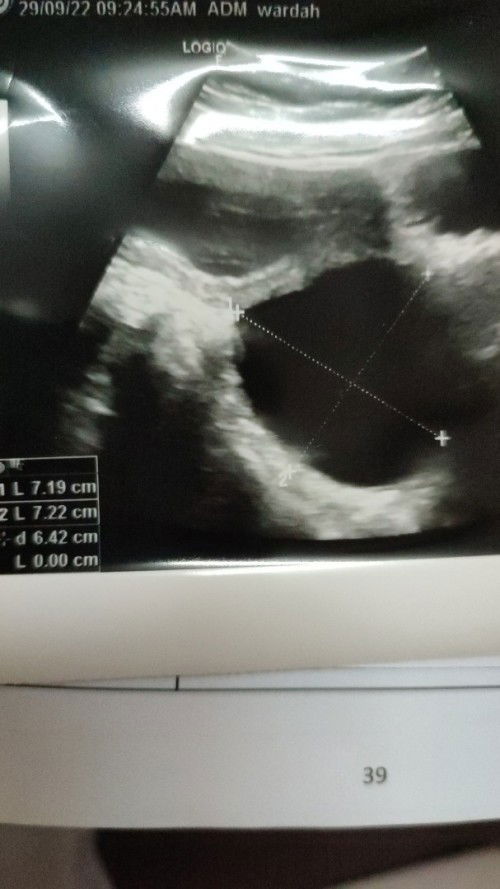

Cyst semasa Hamil

Saya skrg 13 week, dr week 5 sehingga skrg saiz 7x7. saiz statik xmembesar..Dr suggest utk operation minggu ke 16. Kalau x buang kemungkinan besar terpusing tu tinggi sbb saiz cyst lebih dr 5cm Boleh berkongsi pendapat n pengalaman yg berpengalaman dlm operate cyst semasa hamil. Ada risiko x?#seriusnanya #firstmom #firstbaby #pleasehelp Dr bg tempoh 2minggu utk bg keputusan nk operate ke x.